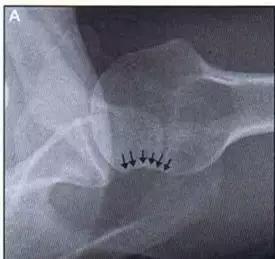

是发生在胫骨平台外侧的垂直撕脱性骨折。这种骨折在前后位 X 线片上显示最佳。屈曲位时膝关节受到内旋*力暴**作用,导致皮质骨撕脱性骨折,这种骨折常发生在运动员身上。

常引起股骨内髁和胫骨平台后内侧骨挫伤,75%~100% 的患者伴前交叉韧带断裂,33% 的患者伴外侧半月板损伤。

一位足球运动员的 Segond 骨折。A 正位片示关节线下方胫骨外侧皮质撕脱(箭头)。B MRI 冠状位 T1 加权像示附着于髂胫带的骨折碎片(空箭头)(来源:Radiol Clin N Am 53 (2015) 737–755,YU,Ohio)